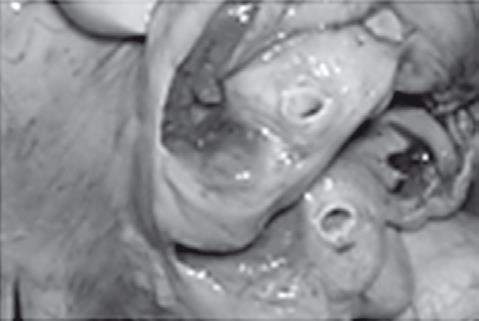

Иллюстрация к книге — Неалкогольная жировая болезнь печени [i_044.jpg]

Гипертрофия миокарда